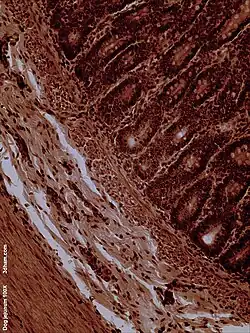

Dog jejunum (magnified 100-fold)

Histology

The jejunum contains very few Brunner's glands (found in the duodenum) or Peyer's patches (found in the ileum). However, there are a few jejunal lymph nodes suspended in its mesentery. The jejunum has many large circular folds in its submucosa called plicae circulares that increase the surface area for nutrient absorption. The plicae circulares are best developed in the jejunum.

- The villi of the jejunum look like long, finger-like projections, and are a histologically identifiable structure.